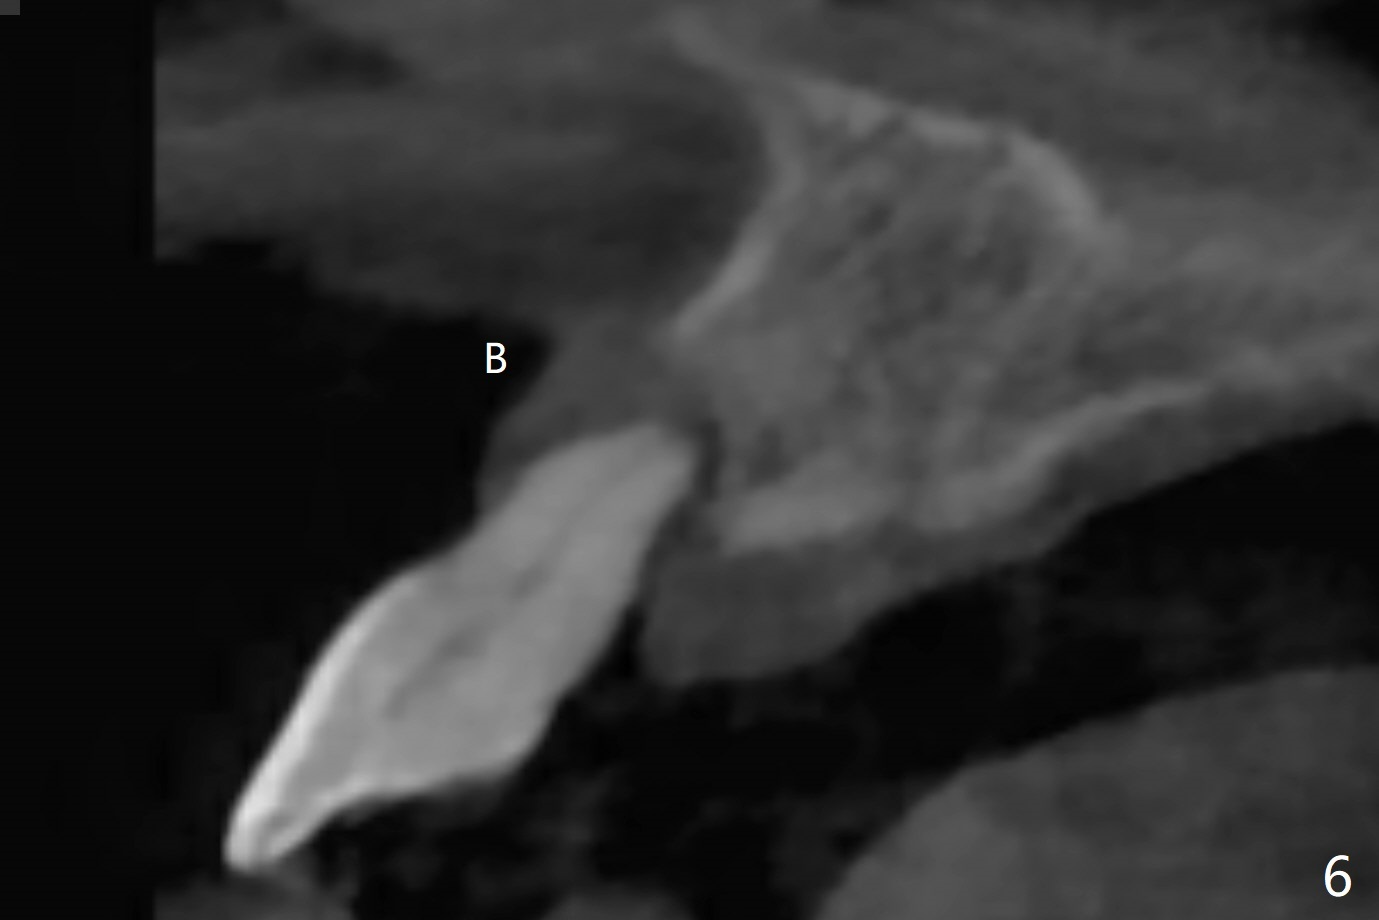

59岁女今天就诊,“上门牙快掉下来”,检查表明右上1延长(图一:长箭头),牙龈退缩(短箭头),红肿(*),颊侧骨板触诊不觉得塌陷(图二)。咬合时,患牙前移(图三),伸长的下切牙(图三,九:1,2)造成咬合创伤。因此拔牙前,将降低下门牙切缘(图四,五(黑色)),为临时牙冠创造足够修复空间。CT冠状切面显示颊侧(图六:B)骨板缺失,可以植入两段式植体(3.5x11.5 毫米),但是最细基台(4毫米直径,图七(粉红色和蓝色))显得太粗,不利于腭侧修复空间形成,而2.5x14(4)毫米一段式植体不仅创造更多颊侧植骨空间(图八(红箭头)),而且由于固有基台直径小(白箭头),容易形成腭侧修复空间。一旦前牙植体永久性修复完成,督促病人做三个第二磨牙植牙修复(图九:7),减少对前牙植牙创伤。临时牙冠不仅解决美观问题,而且固定骨粉,保持颊侧骨板隆起,维持牙龈缘和乳头。在大多数情况下,使用现成树脂牙冠(crown form)制作临时修复物,这个病例牙齿完整,截除的牙冠可以用来做临时牙冠。